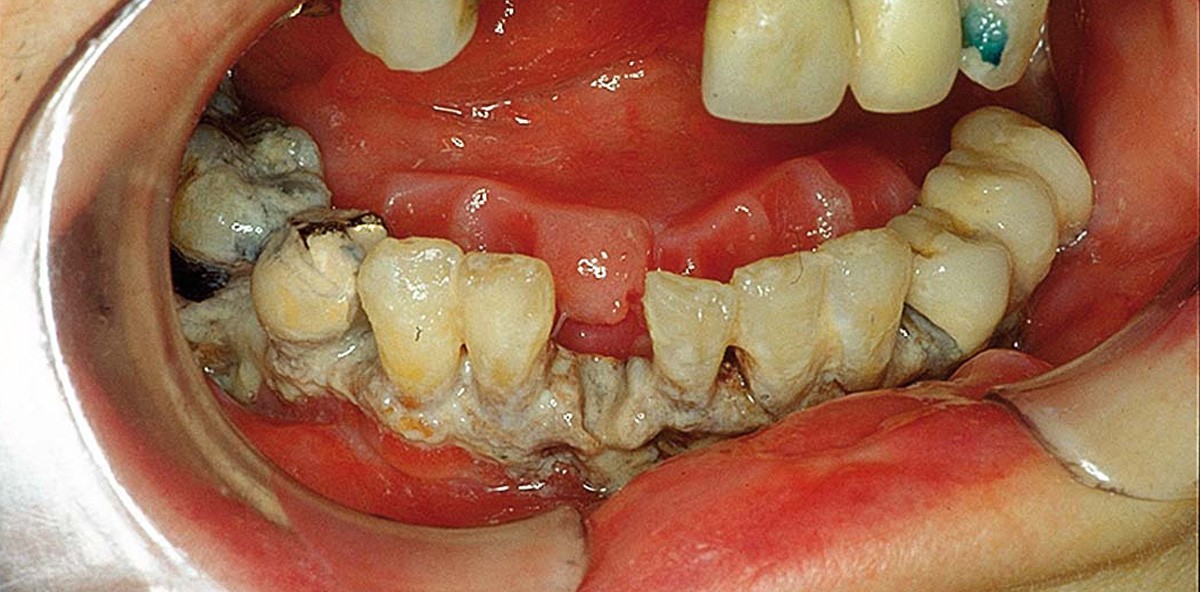

Das typische Erscheinungsbild der Kiefernekrose ist der freiliegende Knochen, der auch über einen längeren Zeitraum (acht Wochen) keine Tendenz der Ab­heilung zeigt. Bei der Osteo­radio­nekrose hat per Definition eine Bestrahlung im Kopf-Hals-Bereich stattgefunden. Hierbei steigt ab einer Bestrahlungs­intensität von über 50 Gy das Erkrankungsrisiko signifikant an. In Abgrenzung zu der Osteo­radio­nekrose hat bei der Bisphosphonat-assoziierten Kieferne­krose keine Bestrahlung in der Anamnese stattgefunden, jedoch ist die Medikamentenhistorie ­positiv auf die Einnahme des Medikamentes. Eine analoge Unterscheidung empfiehlt sich bei anderen Medikamenten­induzierten Kiefernekrosen, wie der RANK-Ligand-Kiefernekrose z. B. durch die Einnahme von

Denosumab®. Neben der Erkrankungsursache lässt sich auch das Erkrankungsstadium für die Bisphosphonat-assoziierte Kiefernekrose klassifizieren. Im Sta­dium I zeigt sich asymptomatischer Knochen ohne Schmerzen und Zeichen einer Entzündung. Im Stadium II wird die Erkrankung symptomatisch. Es treten Zeichen einer Infektion mit Eiter- und Abszessbildung hinzu. Im Stadium III sind zusätzlich eine pathologische Fraktur, Fistelbildung nach extraoral oder Osteo­lysen bis an die Unterkieferbasis  zu finden (Abb. 1–3).